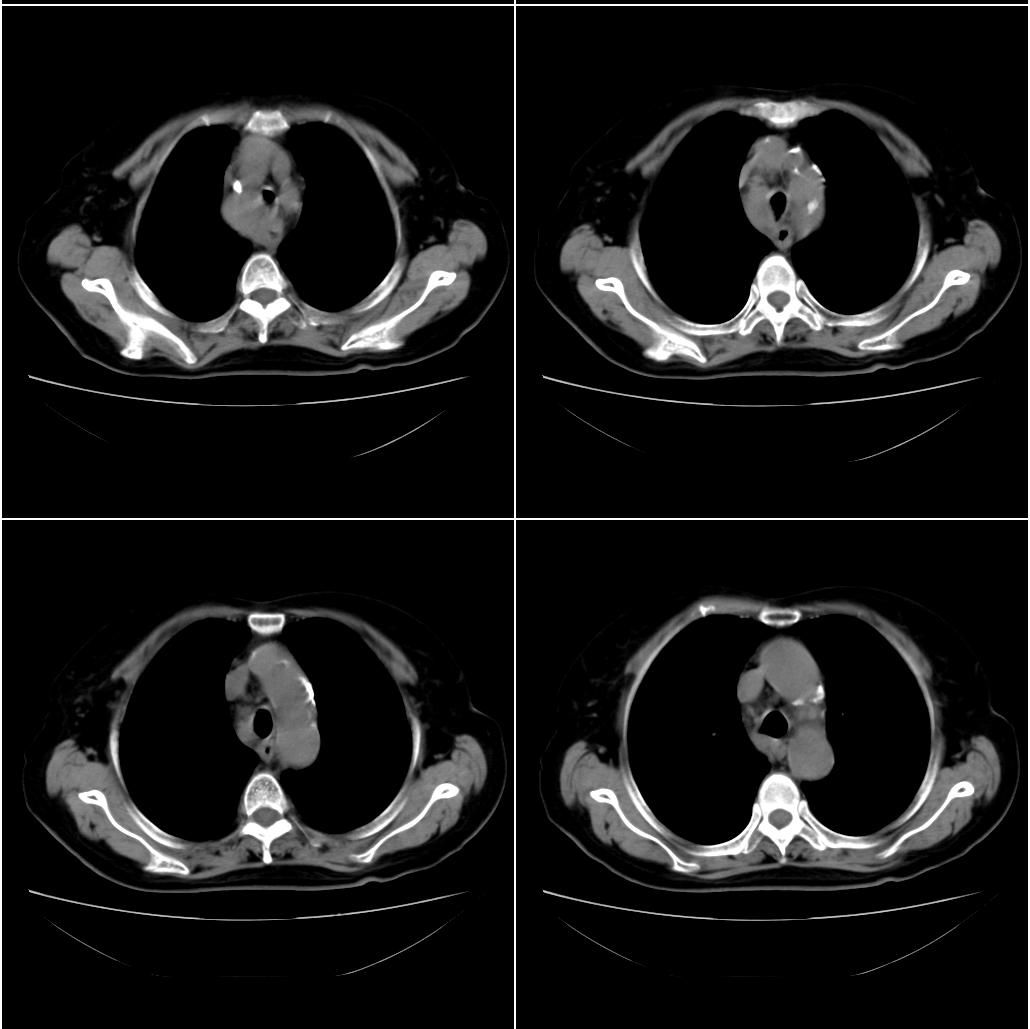

以下是引用sxlcbc在2007-12-23 4:27:00的发言:[br]气管源性肿瘤觉得有点不靠谱啊,看上去气管是受压改变的。更像是上段食管的改变,周围淋巴结肿大,食管受压。看看以下六幅图片:[br]不过,有一点不好理解:食管肿瘤应该有食道症状的,再说食管癌出现周围这么大的淋巴结也不多见啊,如果考虑淋巴瘤倒是更合理一点,这样气管,食管受压改变也许更合理一些。[br][br]